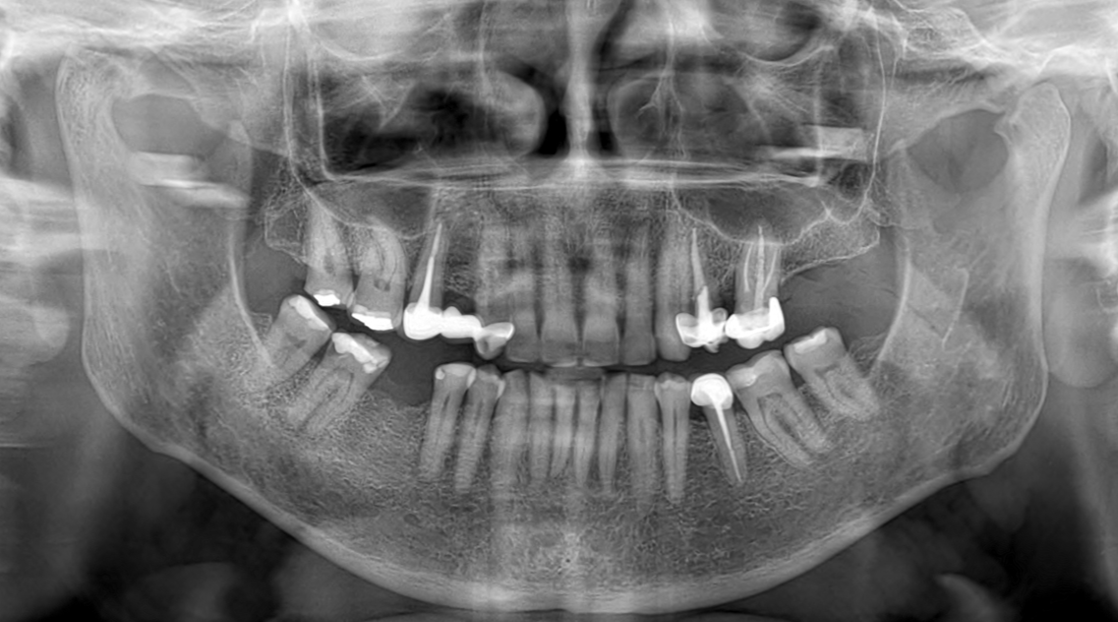

Caso Clinico N° 740 MIXOMA ODONTOGÉNICO (PROBABLE)

22 Jul 2025